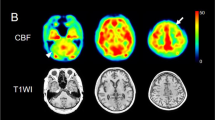

Patient 11: 65-year-old female with CBDS with right predominant rigidity, right pyramidal signs and right limb kinetic apraxia. a, b FLAIR (TR/TE/TI 8,802/147.1/2,200 ms) images show left frontoparietal cerebral atrophy. Hyperintense areas are apparent in the subcortical white matter in the left precentral gyrus (arrows) and less intensely in the postcental gyrus (arrowhead). c ECD-SPECT images show decreased perfusion in the left frontoparietal lobes and in the left putamen

Brain perfusion

Asymmetric hypoperfusion was seen in the frontoparietal lobes on SPECT images in all patients (Fig. 1c), hypoperfusion in the basal ganglia, particularly the putamen, in 11 patients (69%), and hypoperfusion in the thalamus in 14 patients (88%). The side of the hypoperfusion was contralateral to the side more severely affected clinically. SPECT was generally more sensitive in detecting asymmetry than MR imaging. Hypoperfusion was seen in the cerebellar hemisphere in 10 patients (63%), on the side contralateral to the affected cerebral cortex.

According to Kitagaki et al. [21] increased signal intensity changes in the frontotemporal white matter on T2- and proton density-weighted MR images are a useful diagnostic sign of FTD and distinguish this condition from AD. CBD, as well as FTD, Pick’s disease and PSP are tauopathies with tau protein expressed histopathologically. The signal intensity changes in the subcortical white matter in both CBDS and FTD might reflect similar pathological changes. Asymmetric hypoperfusion in the affected cortices was characteristic of CBDS but are not unique to CBDS. Generally, it could be more easily detected than asymmetric atrophy or hyperintensity. Therefore, when it is found, we should pay close attention to atrophy or subtle signal intensity changes in the frontoparietal lobes on the affected side on MR images. Hypoperfusion in the basal ganglia and thalamus ipsilateral to the affected cortices may be due to a remote effect, because no signal or volume change was noted on MR imaging. Hypoperfusion in the cerebellar hemisphere contralateral to the affected cerebral cortices also seems to be remote effect (crossed cerebellar diaschisis). These findings were found in most of the patients. However, we found no significant relationship with the clinical symptoms or MR imaging findings.